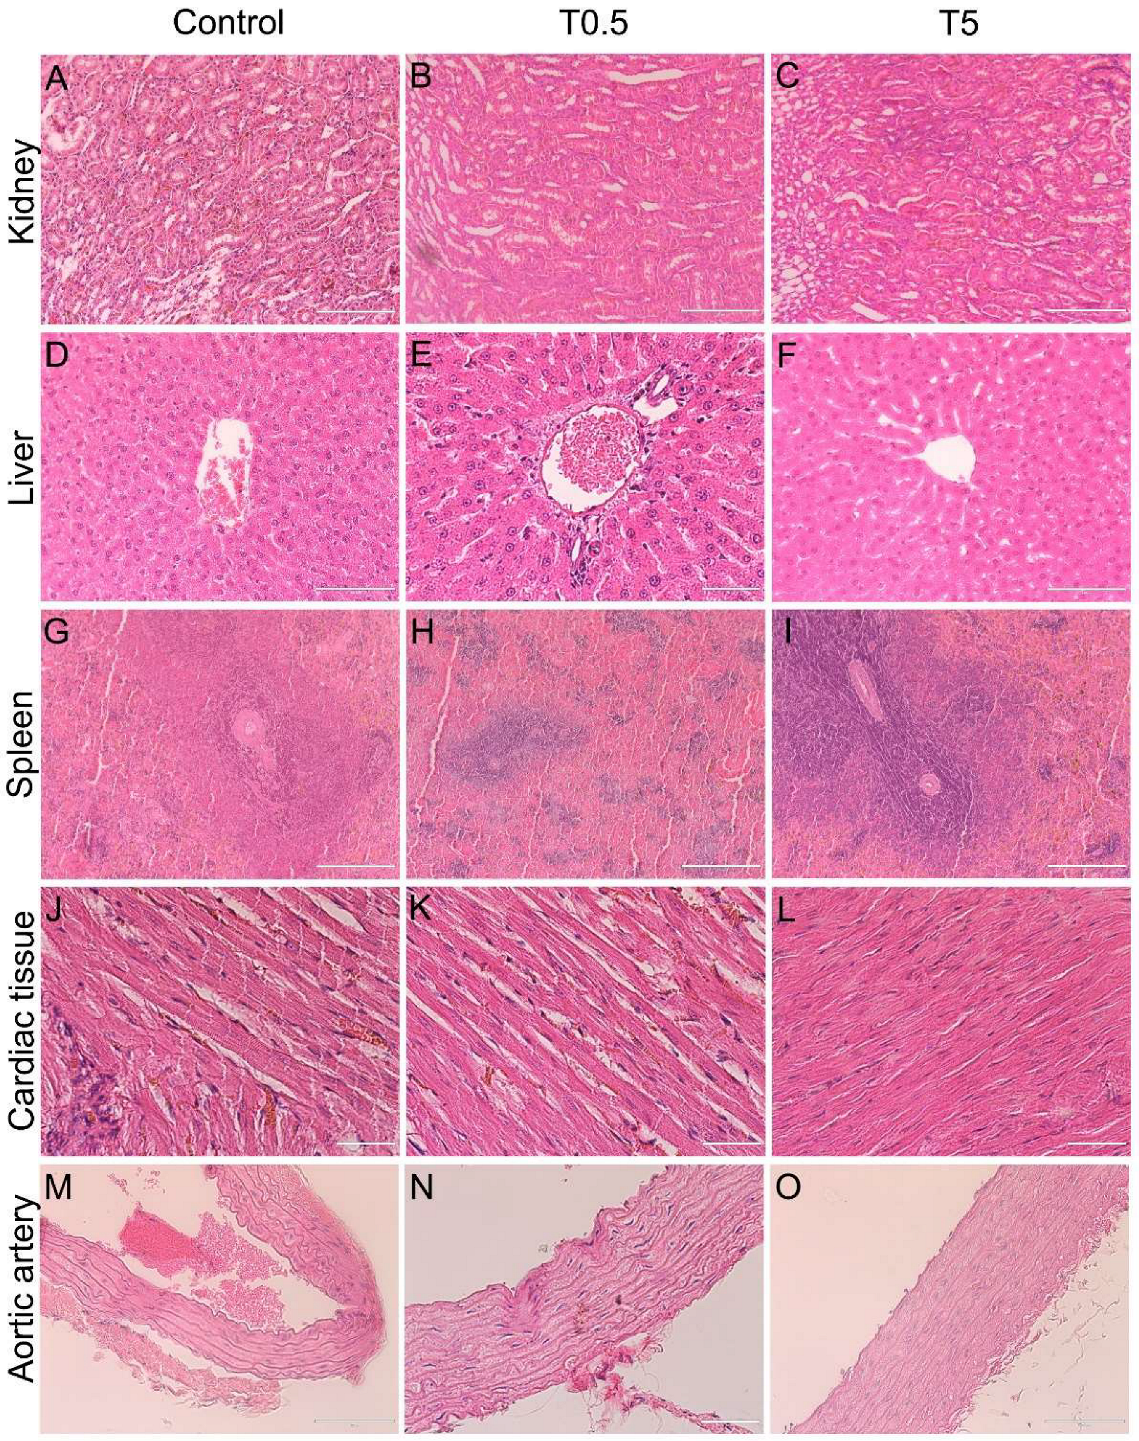

2.7. Organ Micro-Computed Tomography (Micro-CT) and Histological Analysis

3.7. Histopathology